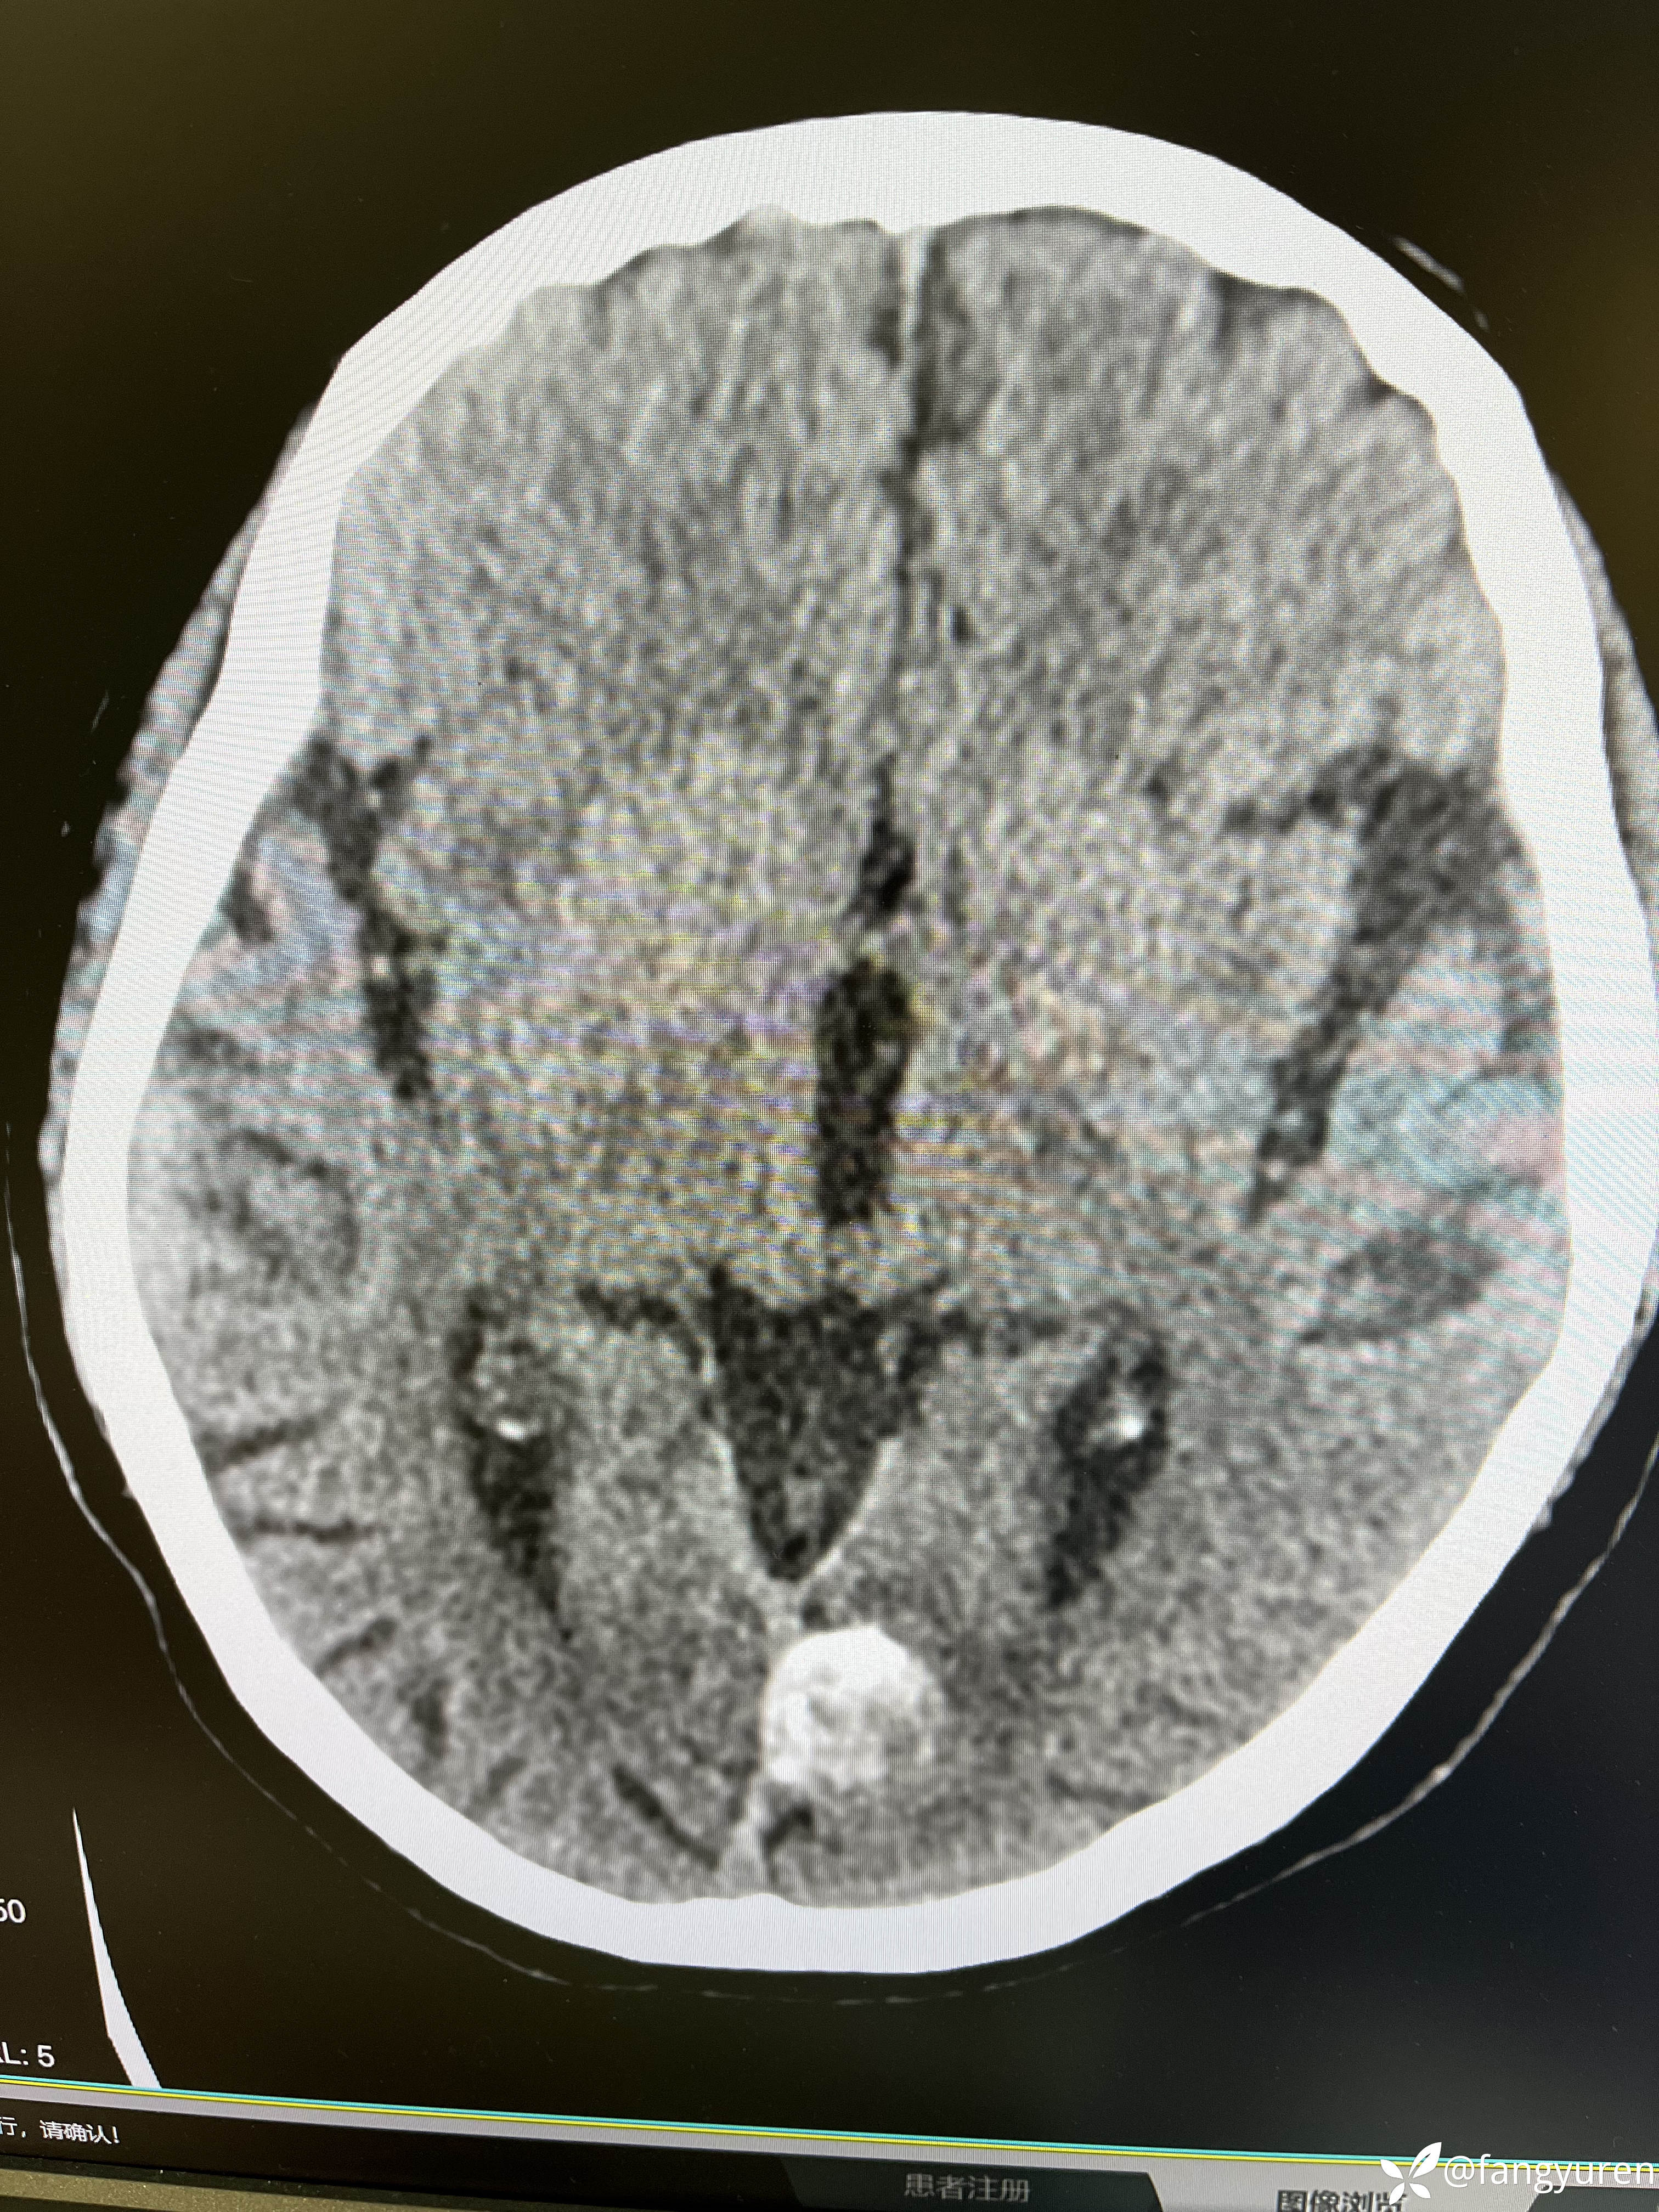

女66,头晕来摄影,发现大脑左侧纵裂旁、左侧额部颅骨下和右侧侧脑室后角见多发类圆形稍高、等、低密度影,部门钙化提示脑膜瘤。如图,蓝圈圈(详细请看视频)所示右侧侧脑室后角见类圆形低密度,周边钙化,考虑是什么,囊状脑膜瘤?多谢老师